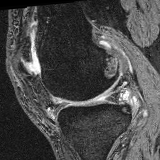

Brain MRI experiment: We also evaluate our method on the MindBooggle101 [4] brain MRIs with 32 cortical regions. We fuse corresponding segmentation labels of the left and right brain hemispheres. MindBoogle101 consists of images from multiple datasets, e.g., OASIS-TRT-20, MMRR-21 and HLN-12. After removing images with incorrect labels, we obtain a total of 85 images. We use 5 images from OASIS-TRT-20 as validation set and 15 as test set. We use the remaining 65 images for training. Manual segmentations in the N=1 and N=21 experiments are only from the MMRR-21 subset; this simulates a common practical use case, where we only have few manual segmentations for one dataset and additional unlabeled images from other datasets, but desire to process a different, new dataset. All images are 1mm isotropic, affinely-aligned, histogram-matched, and cropped to size . We apply sagittal flipping for training data augmentation. We use the same loss weights as for the knee MRI experiment except for , since cross-subject brain registrations require large deformations and hence less regularization.

Results: All trained networks are evaluated using Dice overlap scores between predictions and the manual segmentations for the segmentation network, or between the warped moving segmentations and the target segmentations for the registration network. Tabs. 1 and 2 show results for the knee and brain MRI experiments respectively in Dice scores (%). Fig. 2 shows examples of knee MRI registrations and brain MRI segmentations.

Brain results: Dice scores for segmentation and registration increase by about 2.6 and 3.5 respectively for the cortical structures of the brain MRIs.

Qualitative results: DA achieves more anatomically consistent registrations than the mono-networks on the knee (Fig. 2) and Brain MRI samples (see supplementary material).